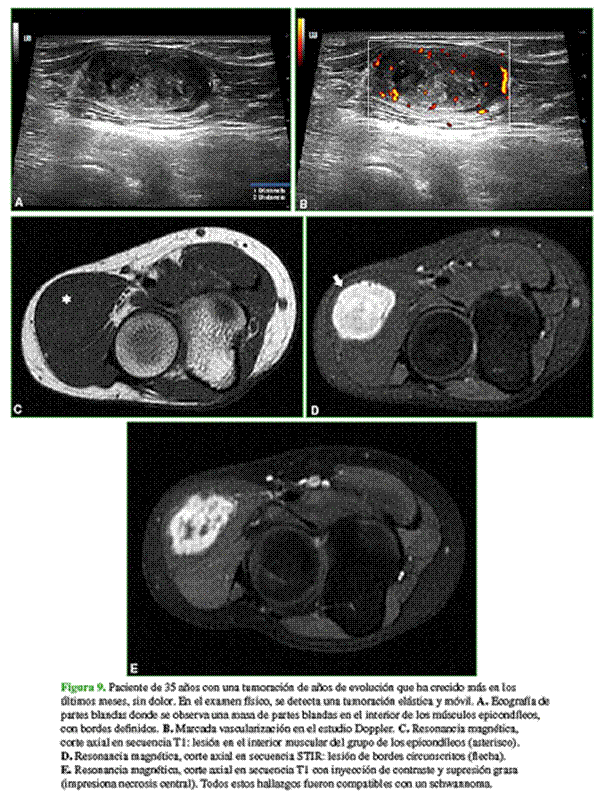

Los diagnósticos diferenciales más frecuentes son: otros sarcomas de partes blandas (fibrosarcoma o sarcoma sinovial), masas de partes blandas (miositis osificante) (Figura 8), schwannoma (Figura 9) y linfoma (Figura 10).